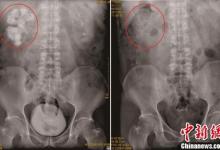

研究發(fā)現(xiàn),新冠病毒感柒組織細(xì)胞的關(guān)鍵所在病毒感染的S蛋白與身體血管緊張素轉(zhuǎn)化酶2(ACE2)蛋白質(zhì)的融合。而胰腺中的ACE2基因的表達(dá)高過肺臟。胰腺中有胰島,胰島能代謝胰島素、調(diào)整血糖值。那麼,新冠病毒會(huì)危害胰腺功能嗎?

法國發(fā)覺一名19歲的男士新冠病人在康復(fù)治療后被確診出身患胰島素依賴型糖尿病患者。科學(xué)研究結(jié)果顯示,新冠病毒感柒會(huì)對胰腺功能導(dǎo)致危害,可能是負(fù)面信息的危害??墒沁@科學(xué)研究并不可以說明新冠病毒會(huì)立即造成病人患上糖尿病患者,另外也不可以清除該病人很有可能身患少見的隱匿性1型本身免疫性糖尿病患者的概率。

可是科學(xué)研究工作人員覺得,新冠病毒根據(jù)與糖蛋白ACE2融合而進(jìn)到到組織細(xì)胞。這類糖蛋白ACE2也存有于身體的胰島β體細(xì)胞中。而胰島β體細(xì)胞在胰島素的造成全過程中的功效十分重要。因而他們覺得新冠病毒很有可能立即功效胰島β體細(xì)胞而對胰腺功能造成不良影響。